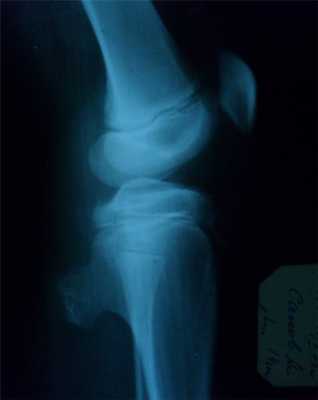

Остеохондрома

- кроме костной ткани содержит и хрящевую, покрывающую поверхность опухоли в виде шляпки,

- исходит из плечевой кости, из мета-эпифизов в области коленного сустава, в головке малоберцовой кости, грудной отдел позвоночника(исходит из дужек или отростков),

- опухоль сидит на широкой ножке и возвышается на кости в виде цветной капусты.

- поверхность ее бугристая, контуры резко очерчены,

- корковое вещество кости переходит на поверхность опухоли или выступает в середину нароста, рассыпаясь на отдельные костные прослойки, идущие в виде лучей к поверхности опухоли,

- рисунок ее не гомогенен, состоит из костных островков, веерообразных пучков и перегородок, лежащих среди светлого фона хряща,

- остеохондромы обладают высоким потенциалом озлокачествления.